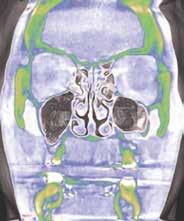

értékelik; azonban ritkán vizsgálják a betegeket az elzáródások eredetére vonatkozóan. Ennek eredményeképpen nagyon gyakran orrelzáródásuk van, és a légutak fizikális vizsgálata vagy képalkotó vizsgálata nélkül kapnak CPAP készüléket, amely a maszk szivárgásával kapcsolatos problémákhoz vezet. Az OSA hatékony kezelési tervének első lépése egy teljes fejre kiterjedő CBCT-vizsgálat elvégzése az elzáródás 4 pontjának meghatározására. (A 4 elzáródási pont (8. ábra) és a CBCT (i-CAT) segítségével történő értékelés részletes magyarázatát lásd az Orthodontic Practice US 2015. márciusi/áprilisi számában [16]). A páciens 4 obstrukciós pontjának – orr-szájpad, orr-garat, velopharynx és oropharynx – vizsgálata kimutatta, hogy a pozíciófüggő apnoe (nyelvalap és velopharynx) mellett orrdugulása is volt (lásd a 9. ábrán látható CBCT-felvételt). Az orrlégúti ellenállás és a BMI a legkorlátozóbb tényezők az OSA-behirdetés

tegek orális készülékterápiával (OAT) történő sikeres kezelésében [17]. Az orrlégúti elzáródás közvetlenül öszszefügg a nappali fáradtsággal [18]. Az i-CAT képalkotó szoftver lehetővé teszi az oropharyngeális légutak volumetrikus értékelését. Ennek a betegnek a kapott adatok alapján súlyosan veszélyeztetett légútja volt, minimum 61,3 mm-rel. A színskála azt mutatja, hogy az értékelés alsó határa 100 mm (9–11. ábra). Kezelési tervünkben OAT (EMA II), fül-orr-gégészeti konzultáció és egy nyomon követő alvásvizsgálat szerepelt. Az FDA által jóváhagyott alvásfogászati készülék 2012. szeptember 5-én került szállításra (12. ábra). A Sibilant Phoneme (Sziszegő fonéma) harapásregisztrációs technikát használtuk a készülék elkészítésének a kiinduló helyzeteként, mivel ez fiziológiai, nem pedig konstrukciós technika. Ez az egyetlen olyan harapásregisztrációs technika, amely bizonyítottan és szakmailag lektorált folyóiratban publikálva jelent meg. Ennek a harapásregisztrációs technikának lényege, hogy megnyitja a légutakat, de amely a legfontosabb, csökkenti azok összeesését [19]. Az OSA-ban szenvedő betegeknél a légzés kizárólag csak alvás közben áll le, ezzel szemben ébrenlét közben soha nem áll le. Így az oropharyngealis légutak térfogata kevésbé fontos, mint azok összeesése. Ez azt jelenti, hogy ritkán van szükség titrálásra, ha a fonetikus harapásregisztrációt kiindulási pontként használjuk. Ez a páciens tökéletes példa erre, mivel az ő készülékét soha nem kellett titrálni. Az orofaringeális térfogatok (13. ábra) az ébrenléti kiindulási állapotban és a harapásregisztrációval csak kis különbséget mutatnak, azonban az

9. ábra: A 3D-s vizsgálat orrkagyló- és orrsövényproblémákat mutat.

10–11. ábra: Légutak számításai különböző nézetekben.